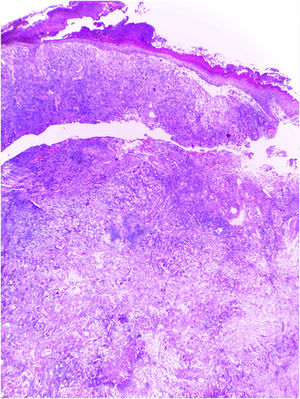

Mulher caucasiana, 54 anos de idade, fototipo Fitzpatrick II, com queixa de lesão dolorosa na região malar direita, de crescimento rápido e comportamento agressivo, surgida havia três meses. Paciente residente em zona rural, agricultora, com relato de exposição solar crônica decorrente do trabalho. Após questionada, negou histórico de trauma no local da lesão, neoplasias cutâneas prévias, imunossupressão e exposição à radiação artificial. Ao exame dermatológico, foi visualizada placa eritematosa infiltrada e dolorosa com exsudação, crostas, ulceração e telangiectasias com extensão para asa nasal direita (fig. 1). Também foi identificado dano cutâneo por exposição solar crônica, manifestado por xerose, melanoses, elastose solar, ceratoses actínicas e perda da elasticidade da pele da face, tórax anterossuperior e membros superiores. As hipóteses diagnósticas iniciais foram carcinoma basocelular terebrante e carcinoma espinocelular invasor. Realizada biopsia incisional da lesão, cujo estudo anatomopatológico evidenciou proliferação maligna epitelioide com ilhas de células claras e áreas de necrose, além de algumas células com citoplasma vacuolado, sugestivo de neoplasia sebácea (fig. 2). Raros focos de queratinização foram identificados, sugerindo carcinoma espinocelular (fig. 3). Coloração especial por PAS com e sem diastase revelou presença de glicogênio citoplasmático, excluindo a possibilidade de diferenciação sebácea.

O CEC de células claras pode ser classificado em três variantes: queratinizante (tipo I), não queratinizante sem conexão com a epiderme (tipo II) e pleomórfico (tipo III).2 Achados histológicos do presente relato são compatíveis com a variante queratinizante (tipo I), de acordo com Kuo.2 Em 2007, nova classificação foi proposta de acordo com a quantidade de células claras no anatomopatológico: casos com ≥ 80% de células claras representam CEC de células claras; casos com <80% e ≥ 50% são definidos como CEC com alteração marcada de células claras; e casos com <50% e >10% são descritos como CEC com alteração moderada de células claras.5 Por essa classificação, a neoplasia apresentada pode ser identificada como CEC com alteração marcada de células claras.

Ao exame anatomopatológico, as células claras atípicas apresentam evidente pleomorfismo nuclear, focos de diferenciação escamosa e áreas de acantólise, com algumas células disceratóticas em meio a espaços pseudoglandulares.1 O principal diagnóstico diferencial é o carcinoma sebáceo, que é marcado por células de citoplasma vacuolado, contendo lipídios, com positividade para fator XIIIa, EMA, adipofilina, receptor de androgênio, citoqueratinas AE1/AE3 e perilipina na imuno‐histoquímica.1,10 Neste relato de caso, o estudo imuno‐histoquímico revelou intensa positividade para citoqueratina 5/6 e p63, com positividade focal para BerEp4, EMA e fator XIIIa. Adipofilina e receptor de androgênio foram negativos (fig. 4). Outros diagnósticos diferenciais incluem triquilemoma, acantoma de células claras, tumor pilar, nevo de células balonizantes, melanoma de células balonizantes e carcinoma metastático renal.6 A cirurgia micrográfica de Mohs é o tratamento de escolha para o CEC de cabeça e pescoço.